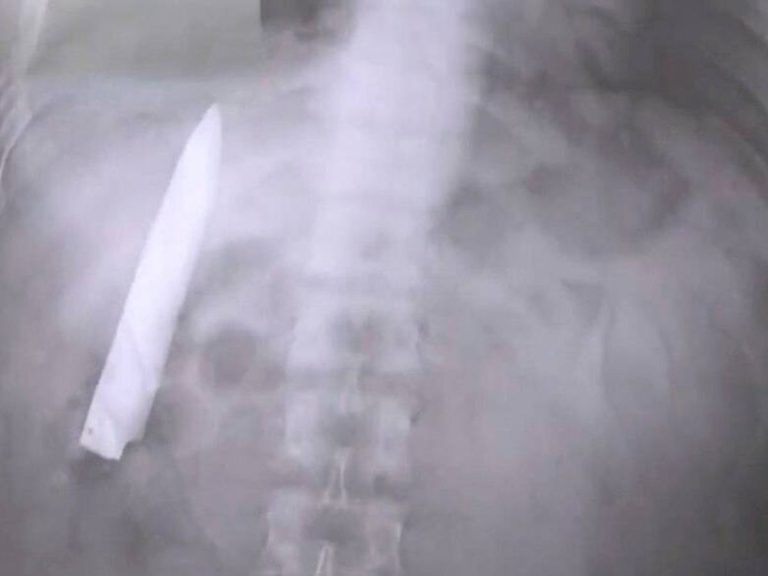

Sorprendente hallazgo: Hombre vivió una década con un cuchillo en el pecho

Un hombre de 44 años en Tanzania descubrió que llevaba un cuchillo en el pecho desde hace una década. Un hallazgo sorprendente tras acudir al médico por una secreción. Conoce este insólito caso.